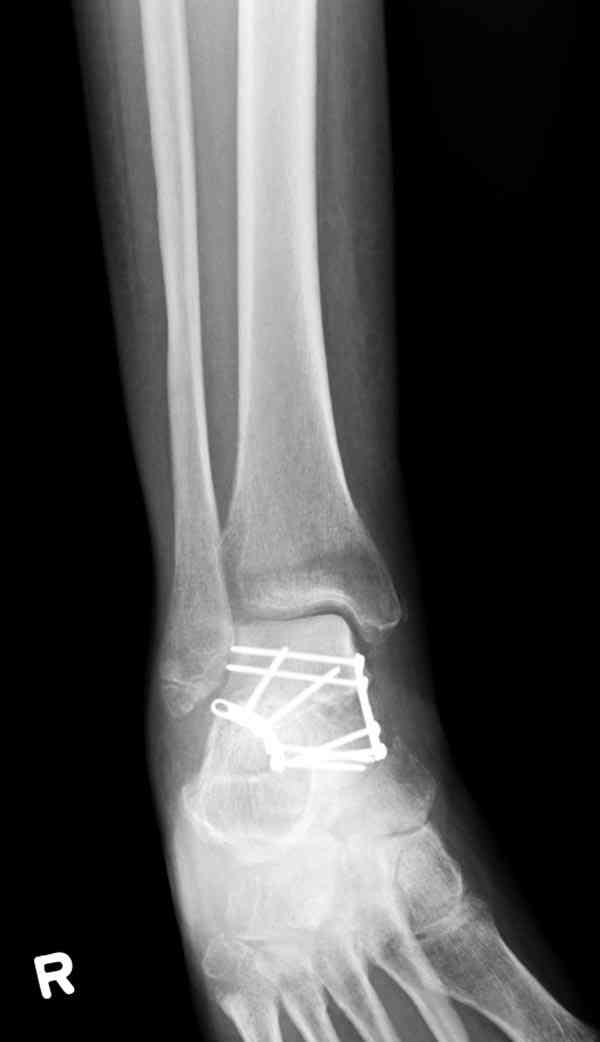

Случай с множественным оскольчатым переломом тарана оперированный из двойного доступа.

Через 2 мес.:

Через 8 мес.:

Через 14 мес.: